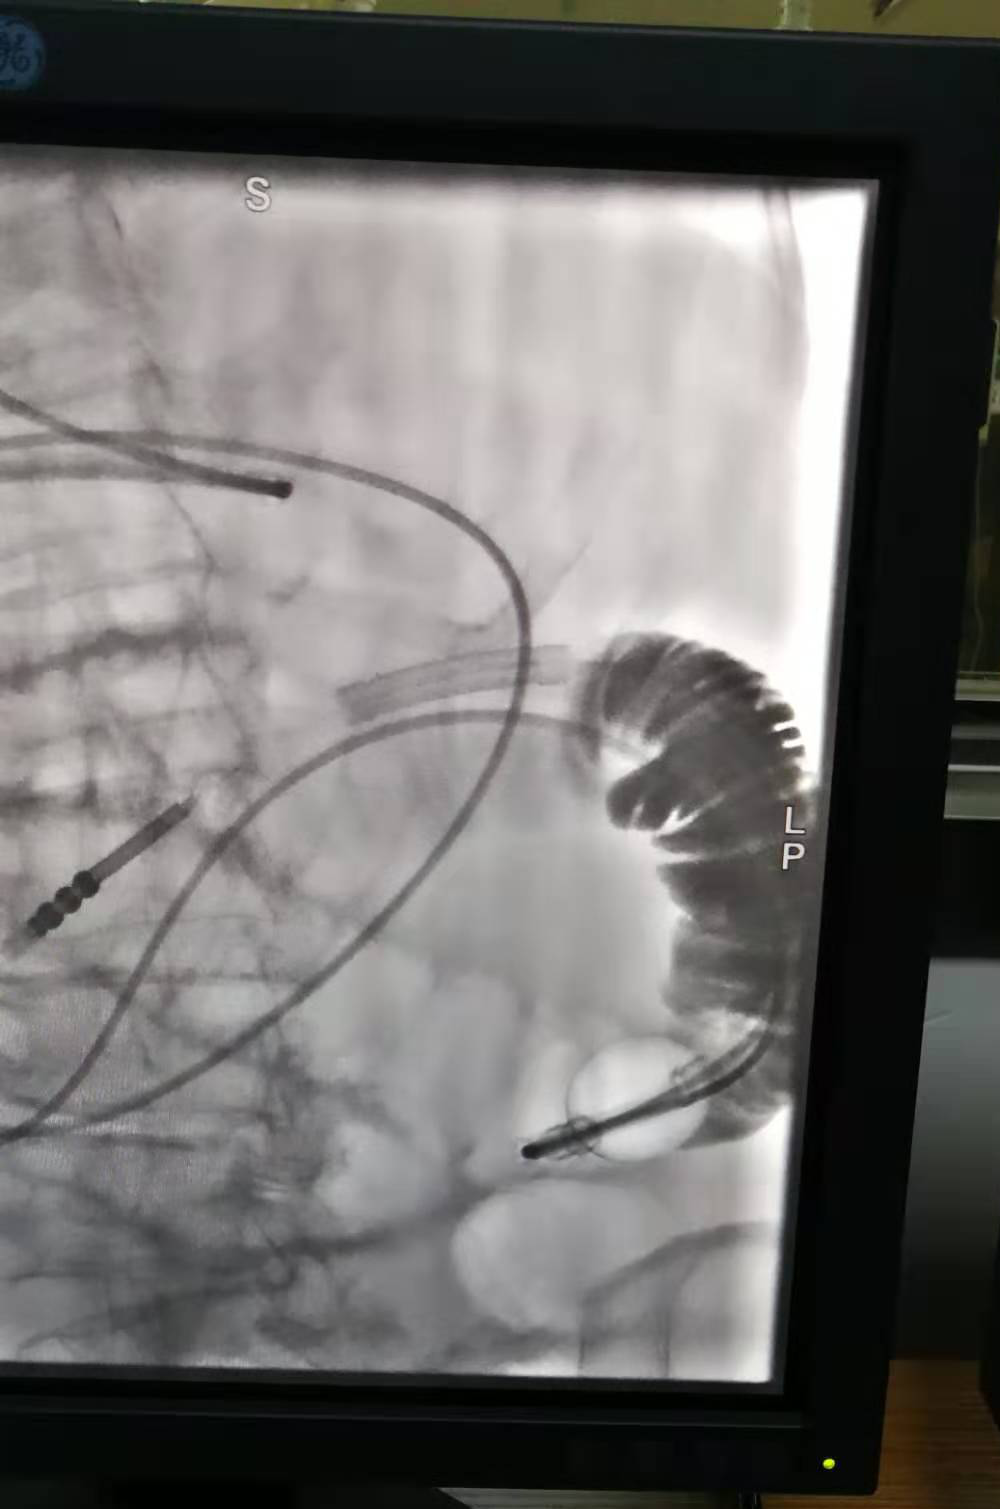

菏澤醫(yī)專附屬醫(yī)院成功為96歲患者開展經鼻腸梗阻導管留置介入手術

2020年11月9日,菏澤醫(yī)專附屬醫(yī)院消化科專家劉慶民、介入中心專家趙金旭及ICU工作人員為一名96歲嚴重腸梗阻患者成功放置經鼻留置腸梗阻導管,標志著菏澤醫(yī)專附屬醫(yī)院在消化科介入治療方面邁入了新的篇章。

因病情比較危重,腸梗阻時間較長,心肺功能差,為爭取治療時間,劉慶民、趙金旭及ICU副主任魏斌、介入科等人員于11月9日夜間加班為老人進行介入下置管,手術成功完成,為病人贏得了寶貴的治療時間。置管后引流良好,腹脹明顯好轉,第二天透視,液氣平消失,梗阻解除。